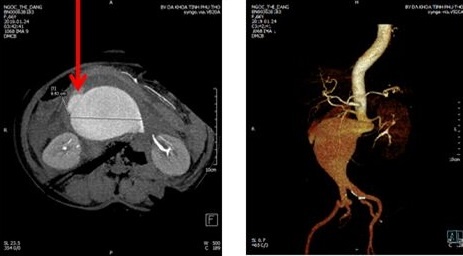

Tại khoa cấp cứu, người bệnh đau bụng, nôn, khó thở, huyết áp 90/60 mmHg, duy trì thuốc vận mạch, kết quả chụp cắt lớp cho thấy khối phình động mạch chủ bụng dưới động mạch thận đường kính hơn 9 cm, hình ảnh khối phình đang chảy máu, tụ máu lớn sau phúc mạc, dịch tự do ổ bụng dạng máu.

| Hình ảnh khối vỡ phình động mạch chủ bụng. |